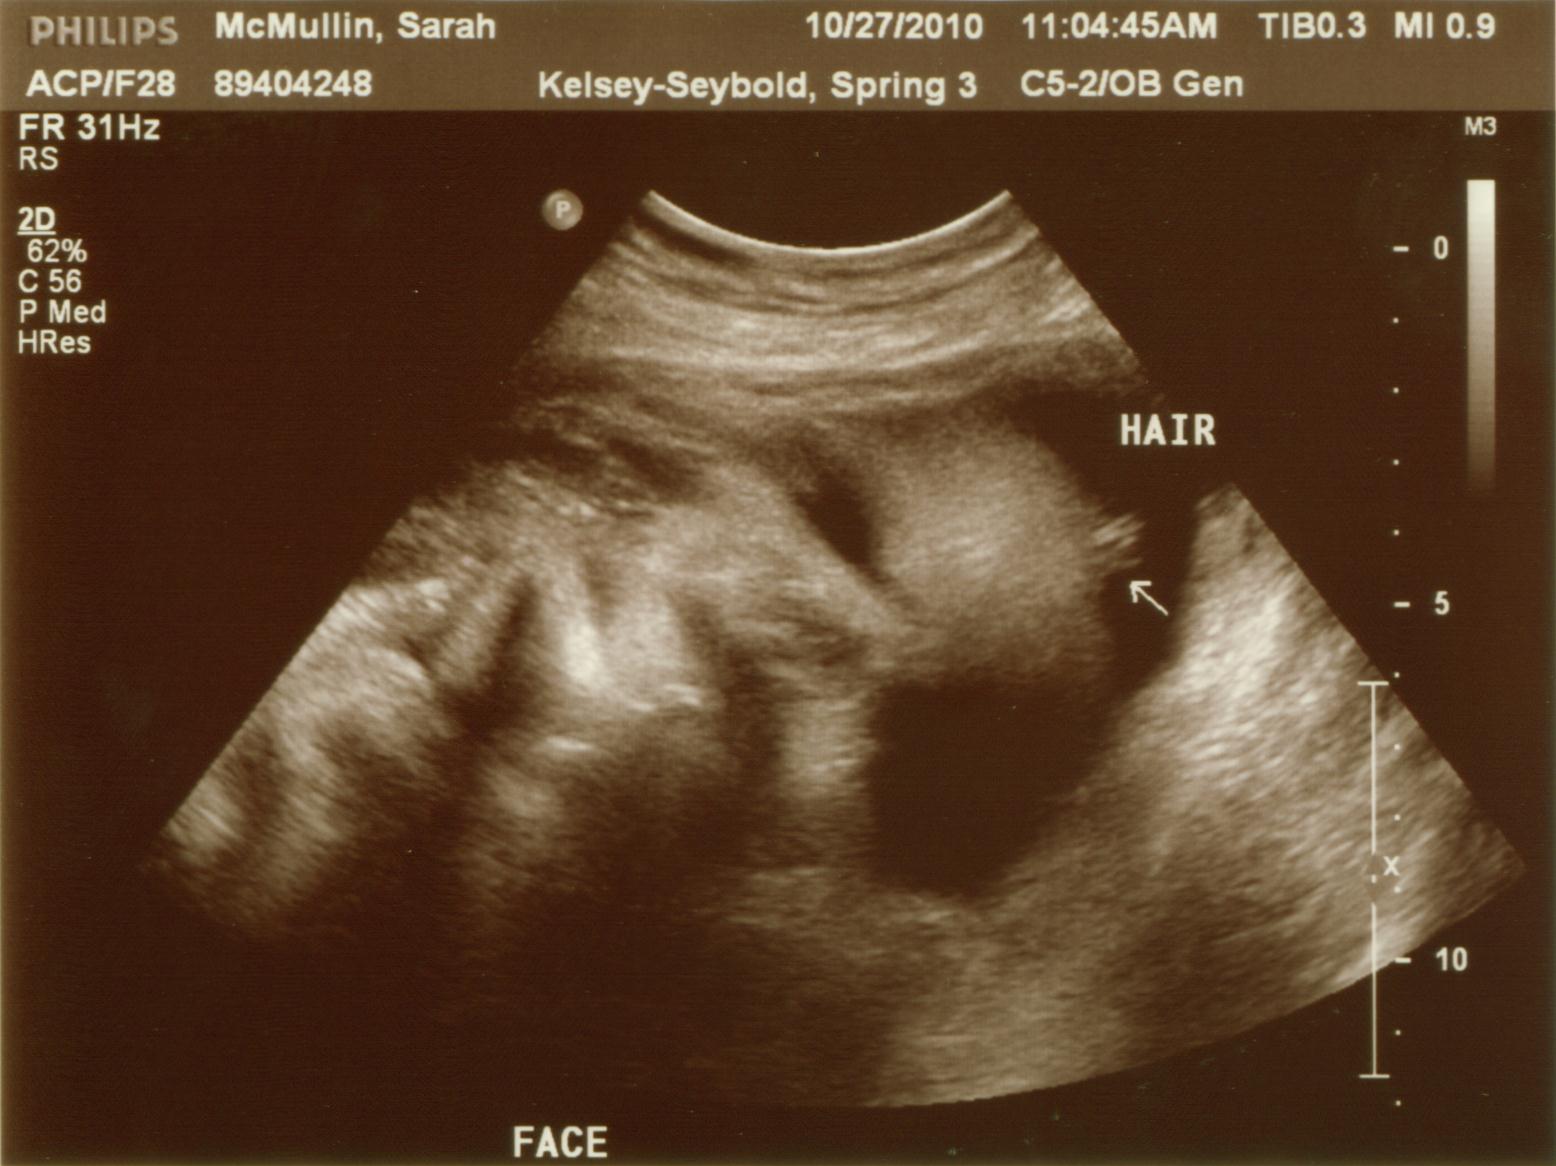

From www.thehahnstadts.com

The Hahnstadts Anatomy Scan + 21 Weeks Skeleton Face Ultrasound 3d ultrasound is an important tool for the evaluation of the fetal face in the first trimester. Using both multiplanar and surface. A transverse view of the head in the plane of the cavum septum. The different sutures and fontanelles are depicted in the coronal ( a ), superior ( b ), and lateral ( c ) views of the. Skeleton Face Ultrasound.